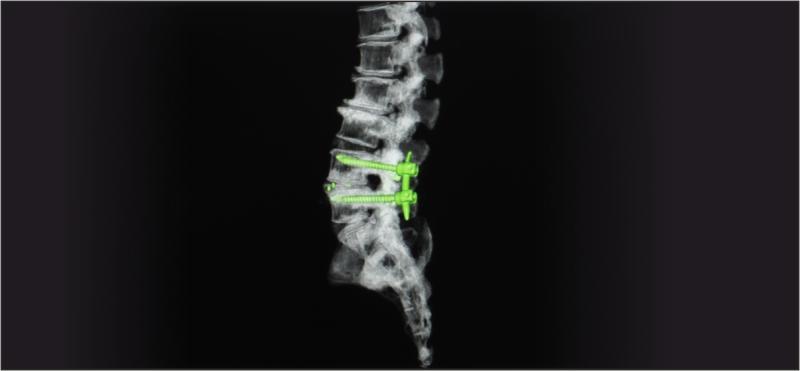

Technological advancements such as dynamic stabilization systems, artificial discs, and interspinous spacers have expanded treatment options. These Spinal Non Fusion Device work by stabilizing the spine while allowing controlled motion, preventing abnormal movements that exacerbate pain or damage. The global aging population, coupled with a growing awareness of minimally invasive surgical options, is contributing to accelerated adoption of these devices worldwide. Furthermore, clinical evidence supporting their efficacy and safety has bolstered confidence among spine surgeons, driving the innovation pipeline forward. As surgical techniques become more refined and new materials such as biocompatible polymers and titanium alloys are increasingly used, the spinal non fusion device market is poised for substantial growth.